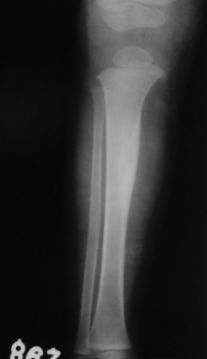

Osteofibröz displazi Campanacci hastalığı; nadir bir hastalıktır, tibia (kaval kemiği) ve fibulayı tutar. Özellikle tibianın 1/3 orta kısmında görülür. Tibia öne ve yana doğru eğilir. Kırık gelişmediği sürece ağrı olmaz. Patolojik kırk konservatif olarak tedavi edilir. Deformiteyidüzeltmek ya da deformite gelişmesini önlemek amacı ile cerrahi olarak tedavi edilir.